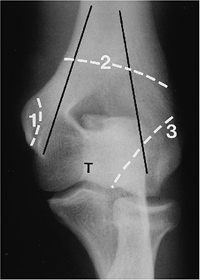

![]() |

FIGURE 8-4 AP radiograph demonstrating the medial and lateral columns (black lines)

with the trochlea (T) between the columns. Fractures may be extra-articular (1), across both columns (2), or intra-articular (3) involving one or both columns. |